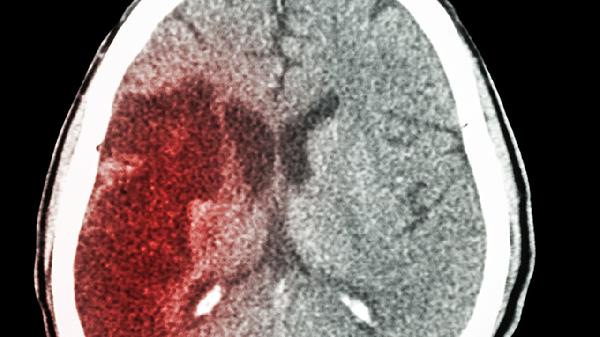

脑梗这个“沉默杀手”来得总是悄无声息,前一秒还在谈笑风生,下一秒就可能突然倒地。但真相是,它从来不会无缘无故找上门。临床数据显示,90%的脑梗其实都有迹可循。